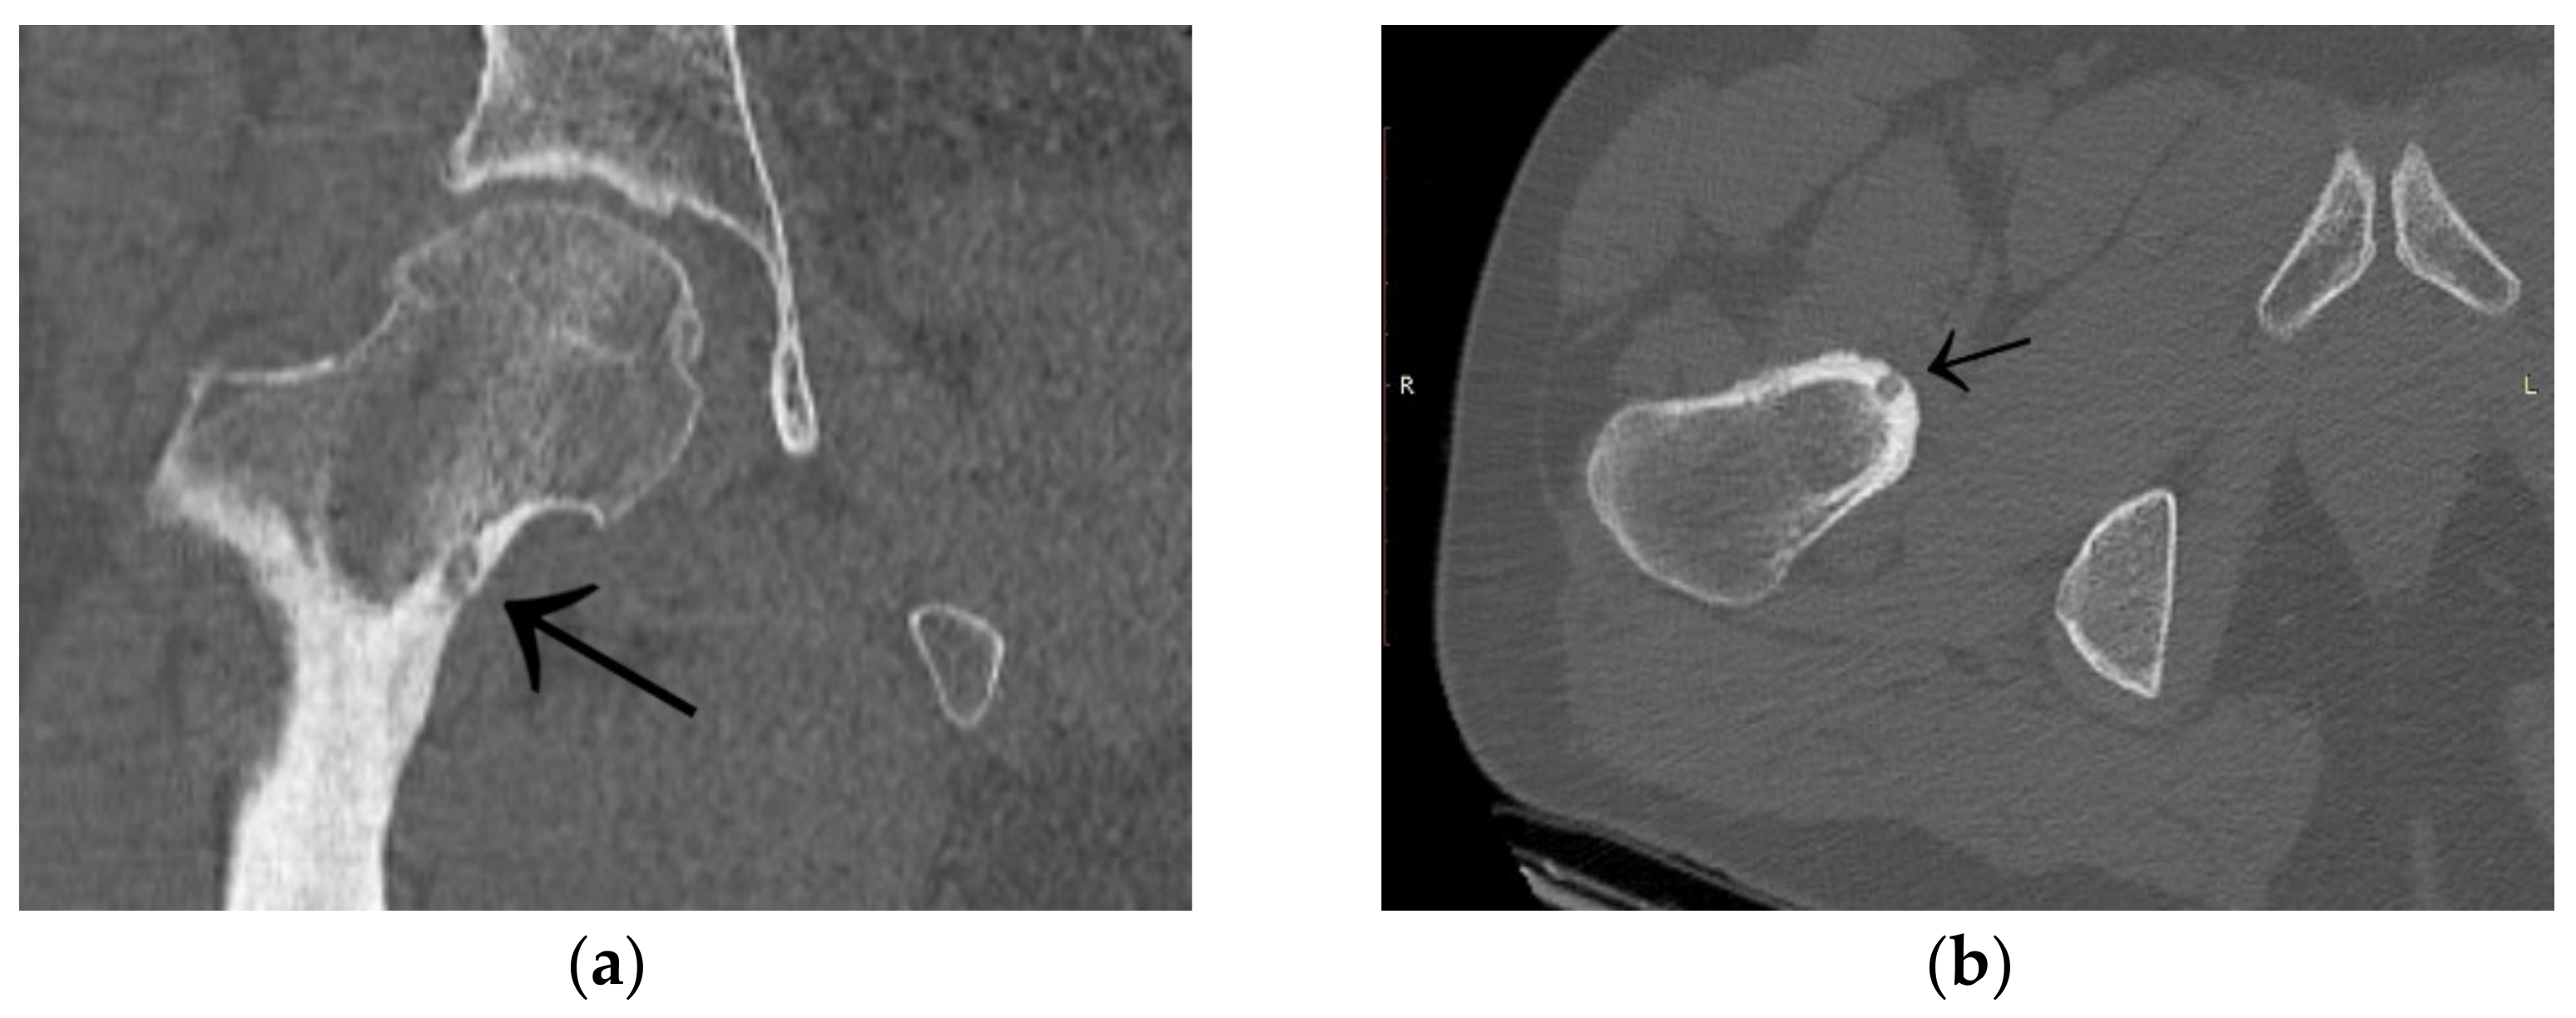

A 30-year-old man was operated on for OO of the right femoral neck. He had a history of night and post-exercise pain in the right hip for 6 months. On physical examination, positive femoroacetabular impingement-specific tests, FADIR (groin pain on flexion, internal rotation and successive adduction of the hip joint) and FABER (groin pain on flexion, external rotation and abduction of the hip joint) were carried out. After a pelvic X-ray and hip MRI scan, a diagnosis of femoroacetabular impingement was made, and the patient was qualified for arthroscopy (Figure 1). The imaging changes suggested a diagnosis of FAI. While awaiting arthroscopy, an ambiguous clinical picture with a history of night pain prompted the attending physician to perform a CT scan of the hip joints. The scan showed a focus of OO of 9 × 6 × 5 mm in the right femoral neck (Figure 2). The patient was treated with thermoablation with intraoperative 3D navigation at the temperature of 90 degrees for 6 min without complications during and after the procedure. An excellent VAS pain reduction score was achieved from 8 points on the day of surgery to 0 at 3 months after surgery. On physical examination 3 months after surgery, the FADIR and FABER tests were negative. The symptoms of FAI disappeared completely.

Figure 2.

CT scan showing a focus of OO (arrows) in the right femoral neck. (a) Frontal CT scan; (b) Transverse CT scan.